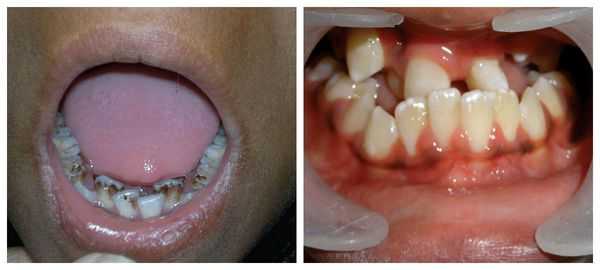

Нарушения зубного ряда происходят из-за раскола верхней челюсти, в результате чего процесс роста зубов становится патологическим: могут наблюдаться пропуски зубов, неправильный угол роста или сдвоенные зубы.

Нарушение развития зубного ряда проявляется пропуском некоторых зубов или наличием дополнительных, неправильным углом роста зубов, склонностью к кариесу. При таких нарушениях может потребоваться ортодонтическое лечение и коррекция прикуса, а иногда - пересадка лишних или имплантация недостающих зубов. У детей с заячьей губой отмечается нарушение процесса формирования звуков, что проявляется расстройством речевой функции (ринолалией). Речь у таких пациентов нечеткая, с выраженным носовым звуком («гнусавостью») и проблемным произношением согласных.